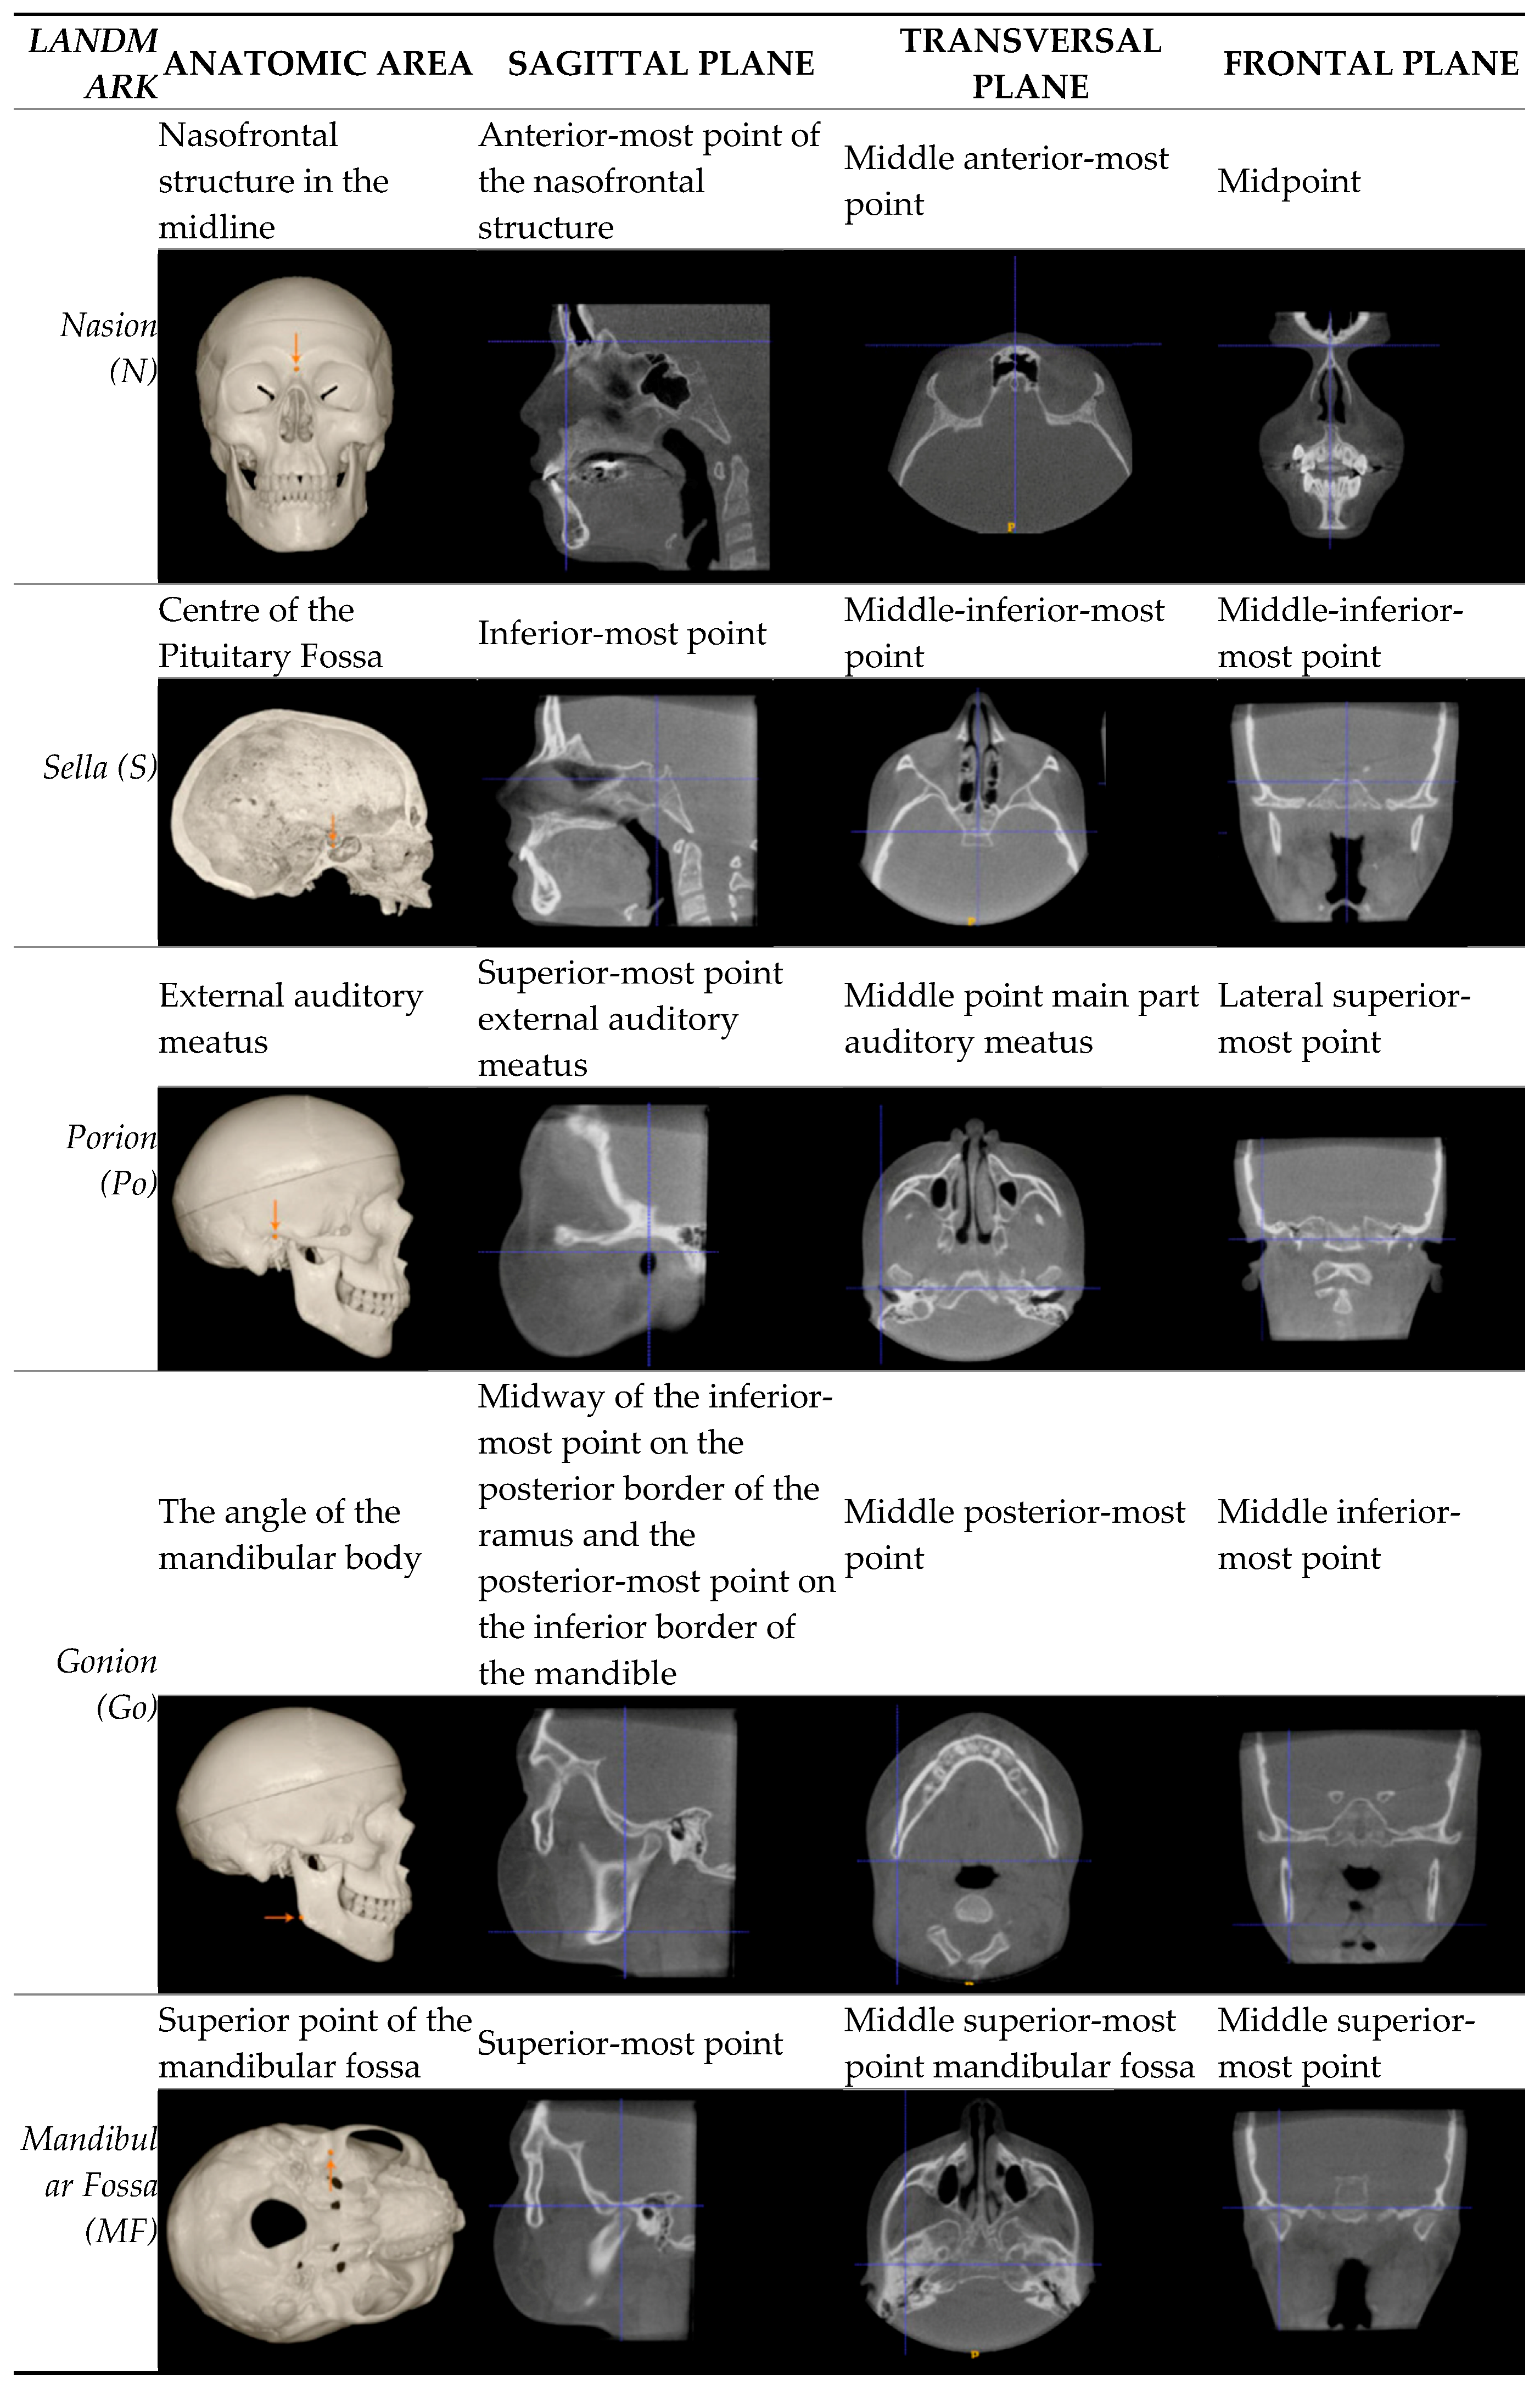

Landmarks and measurements were selected based on the previous study by Meijer et al.22 added to the landmarks that define the Acta plane. The following landmarks were chosen for this research: Nasion (Na), Sella (Se), Basion (Ba), Pogonion (Pog), Gonion (Go), Mandibular Fossa (MF), Orbita (Or), Lateral Orbita (OrbitaLat), Porion (Po), and Root Tip (TL.6). Definition of the landmarks and measurements are listed in Table 1.

Table 1. Description of landmarks.

Preprints 90547 i001aPreprints 90547 i001b